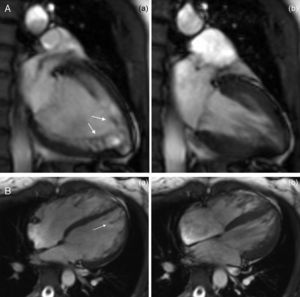

The CMRI revealed marked trabeculation in the apical segments of the LV with a diastolic ratio of noncompacted/compacted layers of 2.6, fulfilling CMRI criteria for noncompaction (Figures 2–4). LV mass was within normal limits and no delayed enhancement suggestive of fibrosis was detected after gadolinium administration.